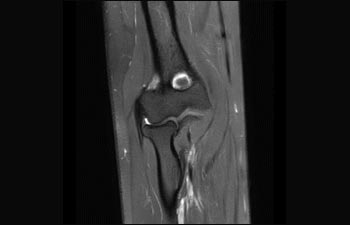

Sehen Sie selbst, was die ersten Nutzer von Ingenia Prodiva 1.5T über ihre Erfahrungen mit dem System und dessen Auswirkung auf ihre radiologische Praxis berichten.

1 Basierend auf einer internen Studie zum Vergleich des Workflows mit einem Achieva System 2 ComforTone ist ab Q4 2017 für den Prodiva 1.5T erhältlich. 3 Basierend auf einer internen Vergleichsstudie mit dem Arbeitsablauf des Achieva MRT-Systems bezüglich einer Mischung aus Gehirn-, Wirbelsäulen-, MSK- und Körperuntersuchungen 4 Normaler Betrieb ist definiert als eine typische Untersuchung mit ununterbrochener Verfügbarkeit von Strom und Magnetkühlung und ohne Wartungsmaßnahmen. 5 Abhängig von den vertraglichen Ansprüchen und der Verfügbarkeit 6 „Andere MR-Systeme“ bezieht sich hier auf Ganzkörper-MR-Systeme mit 60 cm und 1,5 T.